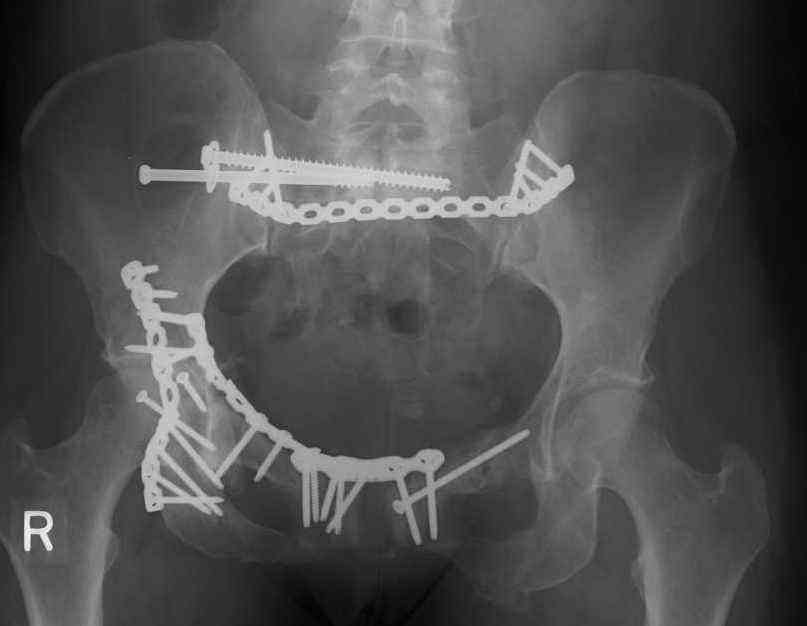

Looking for advice. This is a 48 yo non-smoking female s/p MCC 10 months ago. I do not have the initial injury films. She underwent ORIF as shown on attached file. She is having continued pain in low back/sacral region. Worse with sitting and prolonged walking. Has had pain since surgery. All of her wounds have healed uneventfully. Also has right hip pain laterally. No groin pain. Not aggravated with ROM of the hip. Infection work-up has been negative.

Any thoughts on the broken plate on the pelvic brim and the non-union on the anterior column. Doesn't seem like she's have pain from there.

Maybe remove the disengaged iliosacral screw first to see if she improves?

Thank you...it might help to remove the disengaged and other iliosacral screws then insert longer lag screws into the upper sacral segment and if anatomically feasible into the second sacral segment as well.

You could do it percutaneously and even add an electrical stimulation device if that seems reasonable.

At this point, I'd ignore the right pubic root issue if asymptomatic.

If simple measures such as those above fail, then you could remove it all, take down the sacral fracture site, refix with alternate techniques, and bone graft.